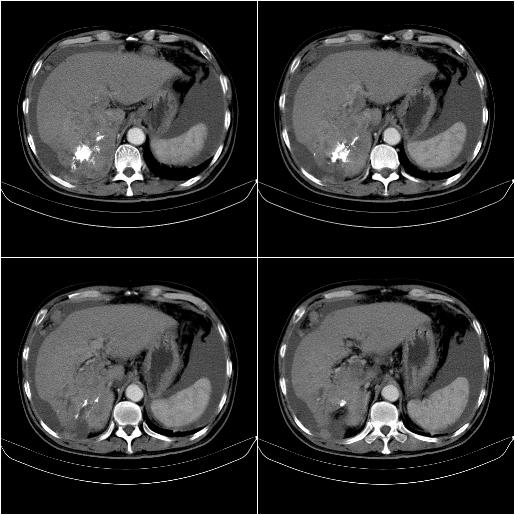

m,67y,肝癌9月,介入术后3月。现腹胀、纳差、腹泻。

情况不好,门静脉癌栓、腹膜转移。

1)肝癌介入治疗术后碘油沉积不良。2)门静脉瘤栓形成,腹膜广泛性转移。3)肝硬化,脾大,腹水。4)慢性胆囊炎。